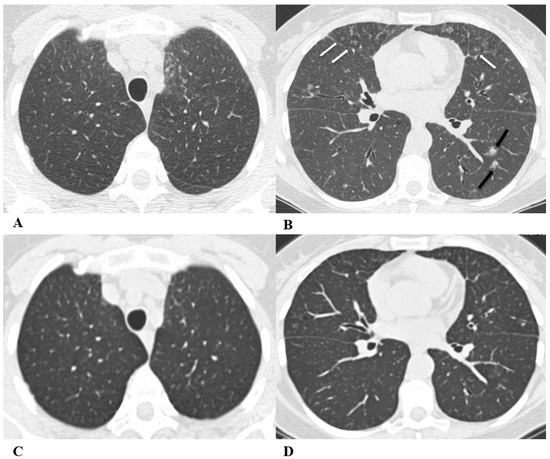

Figure 4.

Acute interstitial pneumonia (AIP)/acute respiratory distress syndrome (ARDS). Acute interstitial pneumonia (AIP) and acute respiratory distress syndrome (ARDS) can be a consequence of both pathogenic intrapulmonary and extrapulmonary stimuli. They are clinically characterized by acute respiratory failure, a consequence of alveolar thickening due to hyaline membrane deposition and inflammatory cells’ infiltration. Both conditions likely represent the same pathology, with AIP probably accounting for some of the idiopathic cases of ARDS.

ARDS from extrapulmonary disease shows bilateral symmetrical changes on CT, whereas in pulmonary ARDS, the opacities tend to be asymmetrical.

The initial form of ARDS can also be classified as diffuse alveolar damage (DAD), followed by the organizing and delayed phases.

HRCT features depend on the phase of the disease, with the possibility of GGOs in the acute phase, and lung cysts and pulmonary opacifications often with an anteroposterior gradient in the delayed phase; complete resolution or evolution into a coarse reticular pattern, traction bronchiectasis and possible bullae, as result of prolonged ventilation, may be found. Sometimes, pleural effusion is observed [9,12,16].

(A–D) A 45-year-old man with rectal carcinoma metastatic to the liver, treated with pembrolizumab. After nearly three months of immunotherapy, the patient suffered acute respiratory failure and interstitial pneumonia suggestive of ARDS in the clinical setting.

Baseline axial chest CT scans (A,B) showed numerous partially confluent areas of GGO, more represented in the perihilar regions as a result of extensive alveolar damage (white arrow), with some dependent asymmetrical peripheral consolidations (black arrow) like an early ARDS pattern, which made it necessary to hospitalize the patient in the intensive respiratory care unit with nose–tracheal intubation.

Three weeks later, CT images (C,D) demonstrated lung architecture disruption, a large component of GGO, reticulation with areas of crazy-paving (black arrowheads), incremented consolidation in the dependent lung and traction bronchiectasis, as seen in the delayed fibrotic ARDS phase.

As accessory findings, note the altered profile of the right ventricle outflow tract (RVOT) and pulmonary trunk with wall calcifications, as a result of multiple reconstructive operations in pediatric age for tetralogy of Fallot.